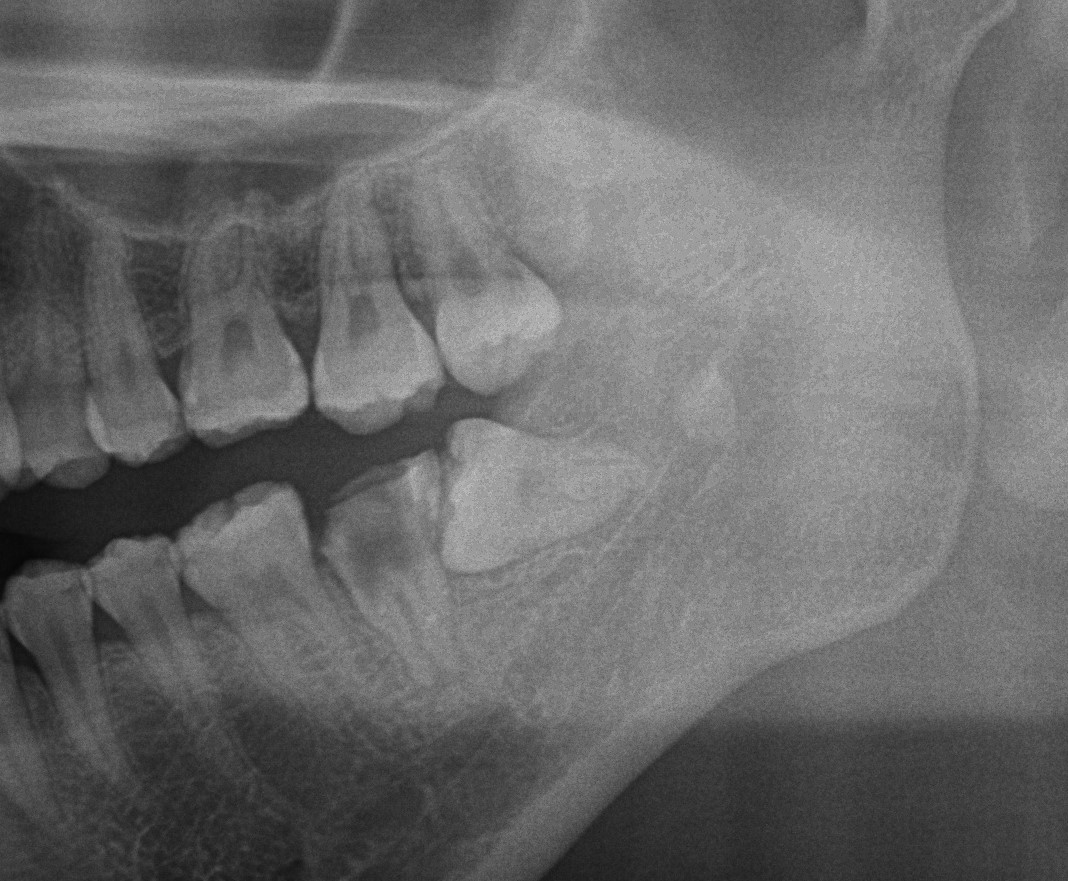

今日はレントゲンについてお話していきます。 歯科のレントゲン撮影は、口内の状態を詳細に調査するための重要な診断ツールです。 歯科レントゲン撮影によって何が分かるのかそれが歯科治療にどのように役立つのかを説明させていただき […]